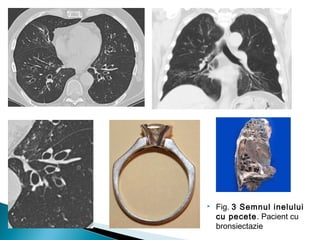

 In mod normal diametrul bronhiei este egal cu diametrul

arterei adiacente ( raportul bronhoarterial=1 )

 Semnul inelului cu pecete apare in momentul in care raportul

bronhoarterial creste

 Acest semn poate fi vazut oriunde in plaman

 Entitati : bronsiectazii

 Ajuta la diferentierea bronsiectaziei de o alta leziune chistica a

plamanului

 Alte semne insotitoare cum ar fi ingrosarea peribronsica, lipsa

de ingustare bronsica si vizualizarea bronhiilor la un 1cm de

pleura contribuie la diagnostic

 Fig. 3 Semnul inelului

cu pecete. Pacient cu

bronsiectazie